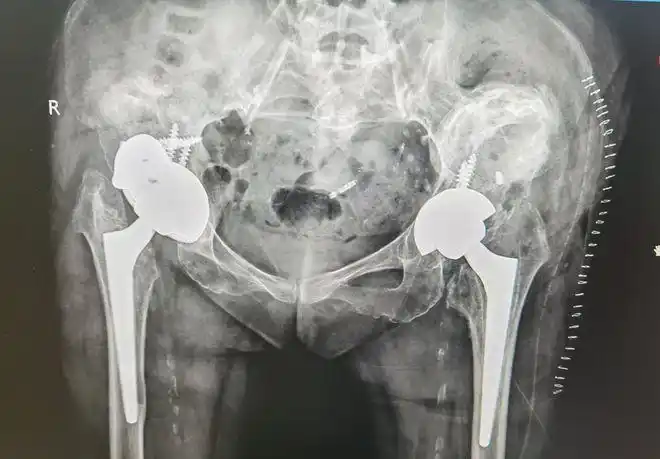

关节假体脱位致女子忍痛20年翻修双髋再次自由行走